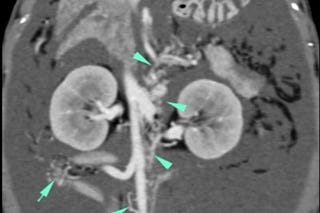

Fístula arterio-portal congénita en una gata

Póster sobre esta interesante anomalía vascular hepática en una gata